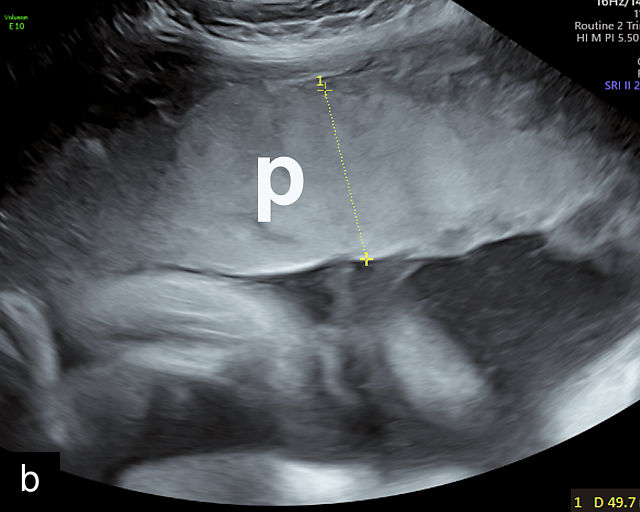

In the early first trimester, trophoblastic tissue appears as an echogenic ring encircling the gestational sac (Figure 1a). By the late first trimester, the placenta becomes recognizable as a distinct structure on ultrasound (Figure 1b). Initially, it presents as a homogeneous echogenic mass (Figure 1b–d) but undergoes progressive differentiation, becoming more heterogeneous as pregnancy advances from the second to third trimester (Figure 1e–g). By the third trimester, cotyledons become discernible, and in the late third trimester, calcifications frequently appear basally and around the cotyledons (Figure 1g).

1

Ultrasound images of development of the placenta (P/p). (a) Trophoblastic tissue appearing as an echogenic ring surrounding the gestational sac at 6 weeks' gestation. (b) Placenta at 12 weeks has become a discrete, uniformly echogenic mass. (c) Placenta at 17 weeks. (d) Placenta at 20 weeks. (e) Placenta at 27 weeks. (f) Placenta at 33 weeks. Increasingly, differentiation and heterogeneous appearance is seen, with demarcation of the cotyledons. Basal calcifications are beginning to appear. (g) Placenta at 40 weeks, showing a distinctly heterogeneous appearance, with clear demarcation of the cotyledons and presence of calcifications.